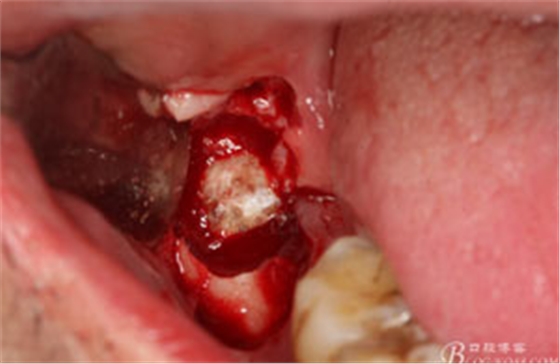

圖9.高速牙鉆分牙:

圖10.先頰舌向橫斷、然后再把牙冠近遠(yuǎn)中向縱分

圖11. “T”型的分牙。